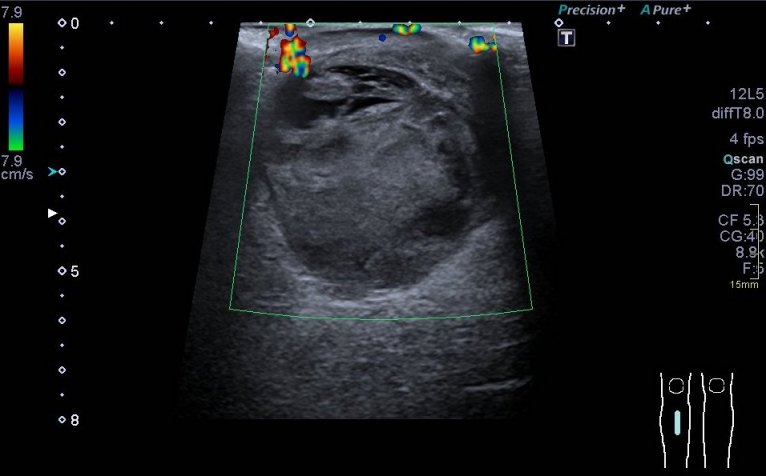

Se realiza estudio ecográfico de la «tumoración» que presenta el paciente la región postero interna de la pierna izquierda, se visualiza lesión heterogénea de 41 x 53 x 54 mm con áreas quísticas localizados sobre todo el tejido celular subcutáneo que presiona al gemelo medial, muy escasa vascularización, y áreas con sospecha de necrosis que en la ecografía se corresponden con imágenes de aspecto quístico.

En estos casos donde la figura patológica está muy a piel, o está muy superficial es imprescindible poner una buena capa de gel entre la piel y la sonda a fin de no presionar en exceso para no deformarla y así poder perder cierta información que puede ser relevante.

Imágenes ecografía: